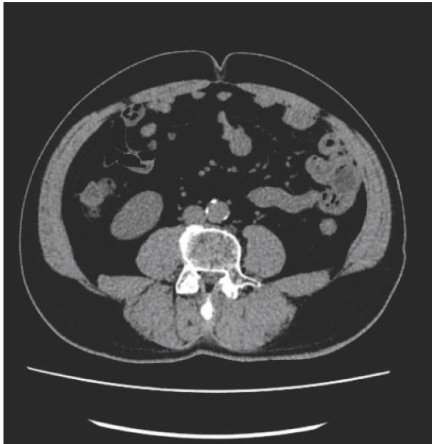

腹部脂肪面积对冠心病的预测价值

The Predictive Value of Abdominal Fat Area for Coronary Heart Disease

Keywordscoronary heart disease; visceral adipose tissue; subcutaneus adipose tissue; fat area